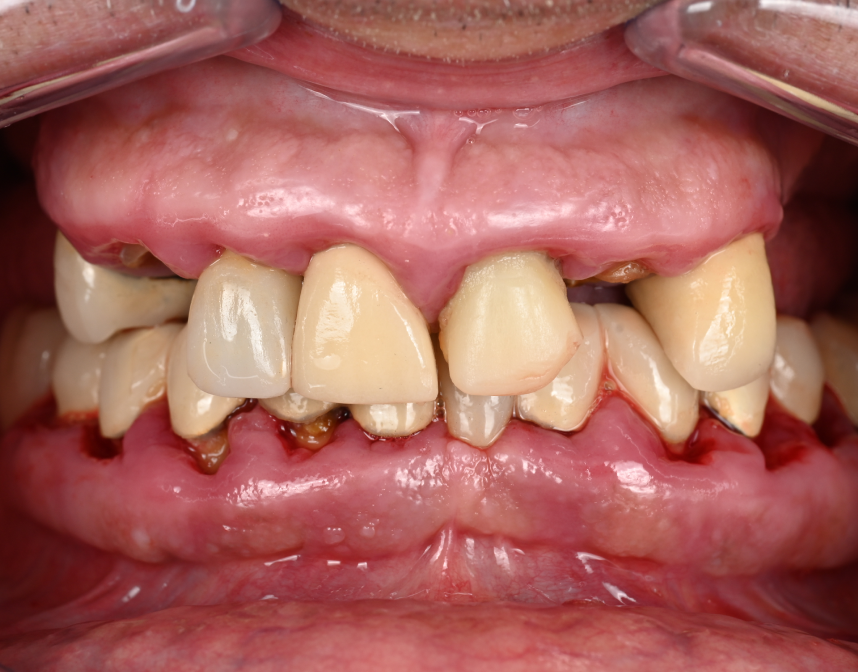

Cas cliniques

Que vous souffriez de problèmes d’occlusion, de perte de dents, de maladie parodontale, ou d’autres problèmes dentaires, une réhabilitation globale pourrait être la solution pour vous. Au cabinet dentaire du Docteur Malthieu à Amiens, nous sommes fiers de pouvoir proposer cette approche intégrée à nos patients.

La réhabilitation globale est une solution complète pour ceux qui ont des problèmes de santé bucco-dentaire multiples et complexes. Elle consiste en un plan de traitement personnalisé, conçu pour traiter toutes les affections dentaires en une seule fois. Cette approche globale permet de restaurer l’harmonie du sourire, tout en améliorant la santé bucco-dentaire de façon durable.